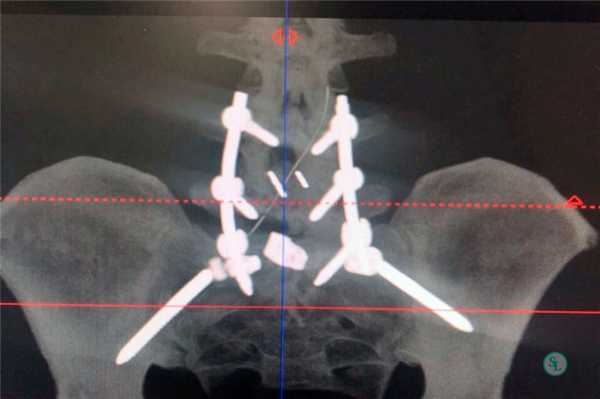

Выполнена операция: декомпрессивная ламинэктомия L4 позвонка, гемиламинэктомия L5 слева, тотальная фасетэктомия L4-L5 с двух сторон, L5-S1 слева, микрохирургическая декомпрессия корешков спинного мозга, транспедикулярная фиксация L4-L5, L5-S1 системой Legasy, задний межтеловой спондилодез L4-L5, L5-S1 имплантатами Fidji.

Диагноз клинический: распространенный остеохондроз грудного и поясничного отделов позвоночника. Дегенеративный стеноз позвоночного канала на уровне Th11-12. Формирующийся артифициальный костно-металлический блок на уровне L4-L5, L5-S1 после транспедикулярной фиксации и заднего межтелового спондилодеза. Вертеброгенная компрессионно-ишемическая миелопатия на нижнегрудном уровне. Нижний комбинированный парапарез, более выраженный слева до дистальной моноплегии. Синдром люмбалгии. Синдром нейрогенной перемежающейся хромоты.

Пациенту был поставлен диагноз: распространенный остеохондроз шейного, грудного и поясничного отделов позвоночника. Дегенеративный стеноз позвоночного канала на уровне С6-С7 справа. Формирующийся артифициальный костно-металлический блок на уровне Th10-L1 после транспедикулярной фиксации. Формирующийся артифициальный костно-металлический блок на уровне L4-L5, L5-S1 после транспедикулярной фиксации и заднего межтелового спондилодеза. Компрессионно-ишемическая радикулопатия С7 справа. Выраженный болевой синдром.